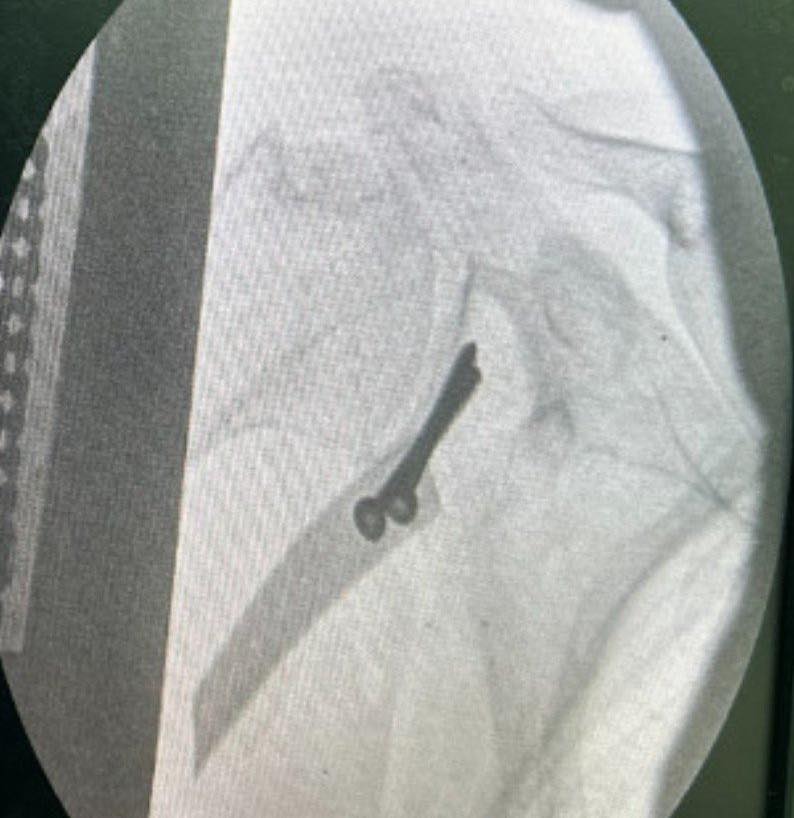

Sau khi thăm khám và thực hiện các chỉ định cận lâm sàng, qua hình ảnh chụp MRI các bác sĩ chẩn đoán bệnh nhân bị trật khớp vai tái diễn, tổn thương chỏm xương, kèm tổn thương ổ chảo xương cánh tay và vỡ mấu động lớn vai phải cần tiến hành phẫu thuật bằng phương pháp Latarjet.

Các nguyên lý của phẫu thuật Latarjet giúp cho tối ưu hoá khả năng chống trật có thể tóm lại 2 hiệu ứng chính, đó là: hiệu ứng nút xương và hiệu ứng treo, phần thấp của cơ dưới vai được giữ lại (treo) do nút chặn xương và phần gân kết hợp xuyên qua gân dưới vai giữ lại, không dịch chuyển lên trên và do đó phần gân dưới vai tham gia vào vai trò chống trật khớp vai tái diễn .

Vì vậy, phẫu thuật Latarjet với việc đưa một phần mỏm quạ và gân kết hợp đầu ngắn gân nhị đầu xuyên qua gân cơ dưới vai và cố định vào bờ trước ổ chảo vẫn được coi là “tiêu chuẩn vàng” trong điều trị trật khớp vai tái diễn”.